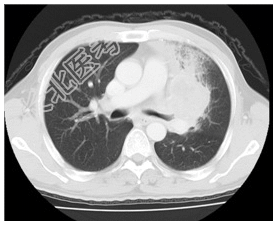

- [材料题] 患者,男性,58岁。咳嗽咳痰1月余,间有血丝痰。无发热及胸痛。查体.锁骨上可扪及肿大淋巴结。左上肺呼吸音稍弱,双肺未闻及干湿性啰音。心脏无异常。行胸部CT增强扫描。